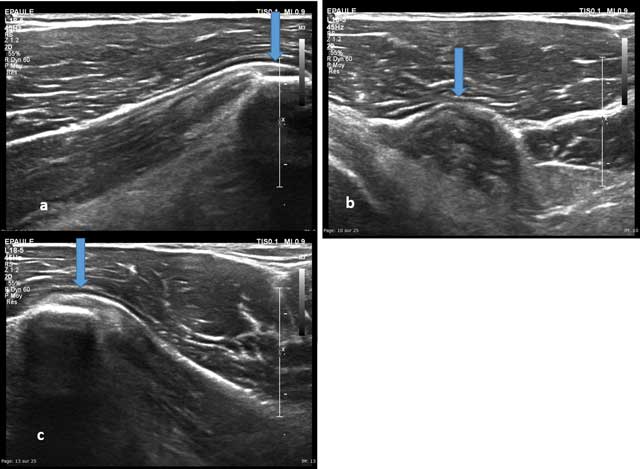

Figure 12

Axial view of the coracoid process with enthesis of the short head of the biceps brachii (a and b) and the coracobrachialis (c).

Figure 13

Axial view of the medial part of the coracoid process with enthesis of the pectoralis minor (arrows).